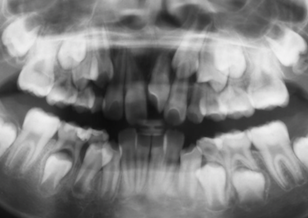

初診時のレントゲン所見では、上顎左側犬歯は隣の側切歯の歯根に重なるように埋伏していました。上下顎歯列にDiscrepancy(永久歯の歯の大きさと基底骨である顎骨の大きさとの不調和)が認められました。埋伏歯に対しての矯正学的アプローチとして口腔外科との連携による治療(インターディシプリナリー治療)として埋伏歯への開窓・けん引治療を行いました。

その後のレントゲン所見では、上顎左右第2大臼歯の埋伏が認められました。

Before Ⅲの写真は、初診時のパノラマレントゲン写真です。